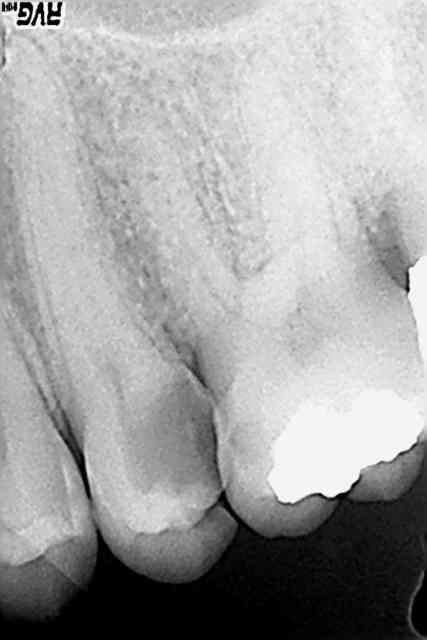

Bon je sais pas comment vous faites. J'ai fait ça ce matin, au protaper, sans mettre très longtemps, sur le contre angle endo, sans rien de spécial dans ma séquence. Et je casse pas. Et j'ai pas de déplacement de canal. Bref je suis entièrement satisfait des protapers.

Edit : 2eme radio sans l'apex, la dent est très longue j'ai eu du mal à viser (26mm). Obturation mixte : fouloir + thermomécanique au mac spadden.

Concernant la première, est ce que ton dernier instrument a été jusqu'à l'apex, ou bien s'est il arrêté juste avant la courbure finale (très serrée).Et ce que l'on observe à la radio serai simplement la fusée de l'obturation qui suivrai le cathétérisme ?

C'est en aucun qu'un une critique ou un jugement simplement une question que je me pose vraiment.

Je me le demande aussi, je suis presque sur d'avoir cathétérisé à 0,5mm de l'apex (localisateur + digue) et par la suite j'ai amené tous mes instruments à cette LT (simplement S1, S2, F1, F2, pas de SX/endoflare, pas d'US pas de gates). Bon j'ai jeté les instruments après usage :).

Par contre pas de radio entre préop et obturation, la patiente avait juste RDV pour une "douleur au froid". On comprend pourquoi.

Maintenant le gutta condensor 35/10ème sur 20 mm ça pousse fort en effet...peut être que les instruments n'ont pas vraiment pénétré le crochet. C'est peut être aussi la limite de la zone "tassée" qu'on voit, les fouloirs et condensors sont droits contrairement aux protapers.

J'ai eu la surprise sur la radio finale, je n'avais pas vu ce crochet sur la préop.

et par contre c'est la même 25, qui a bien 2 canaux (radios + ou - angulées)